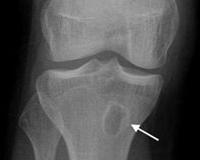

• Рентгенография. В типичных случаях на изображениях видна единственная изолированная округлая костная полость правильной формы, длина которой соответствует длине кости. Полость окружена полосой остеосклероза. Метафиз немного утолщен за счет слоев надкостницы.

Абсцесс Броди дифференцируют от обычного хронического остеомиелита, костно-суставного туберкулеза, костной кисты, десны, остеоид-остеомы, эозинофильной гранулемы. Для распространенного остеомиелита характерны секвестрация, образование грубых надкостничных разрастаний, чередование участков остеосклероза и остеопороза. Костная киста более крупная, многокамерная.

При костном туберкулезе очаг меньше, неправильной формы, с губчатой секвестрацией, склонен к быстрому разрыву на поверхности кожи или в полости сустава. Десны в подавляющем большинстве случаев множественные, имеют менее гладкие контуры. В эозинофильных гранулемах на изображениях видны картонные очертания, менее выраженная граница склероза. Остеоид-остеомы проявляются постепенным усилением боли.